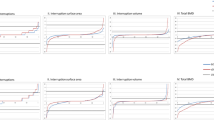

See Table 3 for details of the values and results of the longitudinal statistical analyses for the HR-pQCT disease main effect, representing the overall differences between RA and NRA participants independent of time at all three sites. In summary, differences in density included: RA participants had significantly lower trabecular bone density at all three sites (varying from 15.4 to 10.9% lower), significantly lower cortical bone apparent density at both MH sites (MH2 8.7% and MH3 9.9% lower) and significantly lower cortical bone material density at the MH2 site (MH2 3.9% lower). Differences in cortical bone micro-structure included: At the UUD site RA participants demonstrated significantly greater variability in cortical thickness (9.3% greater variability in thickness) and significantly less cortical bone volume at both MH sites (MH3: 3.8% MH2: 4.5% lower). Trabecular bone micro-structure differences included: At all three sites RA participants had significantly larger and more variable sized spaces between trabeculae (varying from 11.9% to 16.0% larger spaces and 22.9% to 35.2% more variable sized spaces). At all three sites RA participants trabecular matrix was also significantly more rod- verses plate-like shaped trabecular matrix (SMI varied from 20.8% to 84.1% greater) with significantly lower trabecular bone volume (varying from 12 to 8% lower). At the UUD and MH2 sites, RA participants also had significantly fewer trabeculae (UUD 7.2% lower; MH2 9.0% lower). Whereas, at the UUD site RA participants also had trabecular that were less connected (13.0% less trabecular connectivity). Figure 2 shows plots (mean +/− SEM) for selected density and microstructural variables with consistent differences between RA and NRA participants across the three ROIs examined in this study, as well as, notable differences in the density and micro-structure values of the two MH head ROIs and the UUD ROI. To illustrate further the differences between RA and NRA participants, Fig. 3 shows the typical visual differences in trabecular bone micro-structure seen in 3-Dimensional reconstructed images of the UUD and MH sites in age- and sex-matched RA and NRA study partners.

Common Changes in Density and Micro-structure across Regions of Interest: Bar graphs [mean (SEM)] showing differences between rheumatoid arthritis (RA) and Non-RA (NRA) participants for selected density and microstructural variables with consistent differences across two or three of the regions of interest examined in this study. This figure also illustrates regional differences density and microstructural in the two MH compared to the UUD ROIs